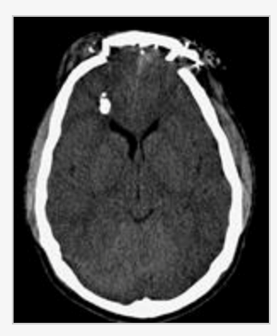

A 65-year-old man presents with one week history of agitation and confusion. He sustained a generalized tonic-clonic seizure and is hallucinating. On exam, he is febrile, confused and has a left pronator drift with hyper-reflexia. An MRI of the brain is shown (figure). Which of the following is the most likely diagnosis?

a. Herpes simlex virus

b. Low grade glioma

c. Neurosyphilis

d. Hemorrhagic stroke

e. Sarcodosis

A

A 65-year-old man presents with one week history of agitation and confusion. He sustained a generalized tonic-clonic seizure and is hallucinating. On exam, he is febrile, confused and has a left pronator drift with hyper-reflexia. An MRI of the brain is shown (figure). Which of the following is the most likely diagnosis? a. Neurosyphilis b. Hemorrhagic stroke c. Low grade glioma d. Herpes simlex virus e. Sarcodosis

d. Herpes simlex virus